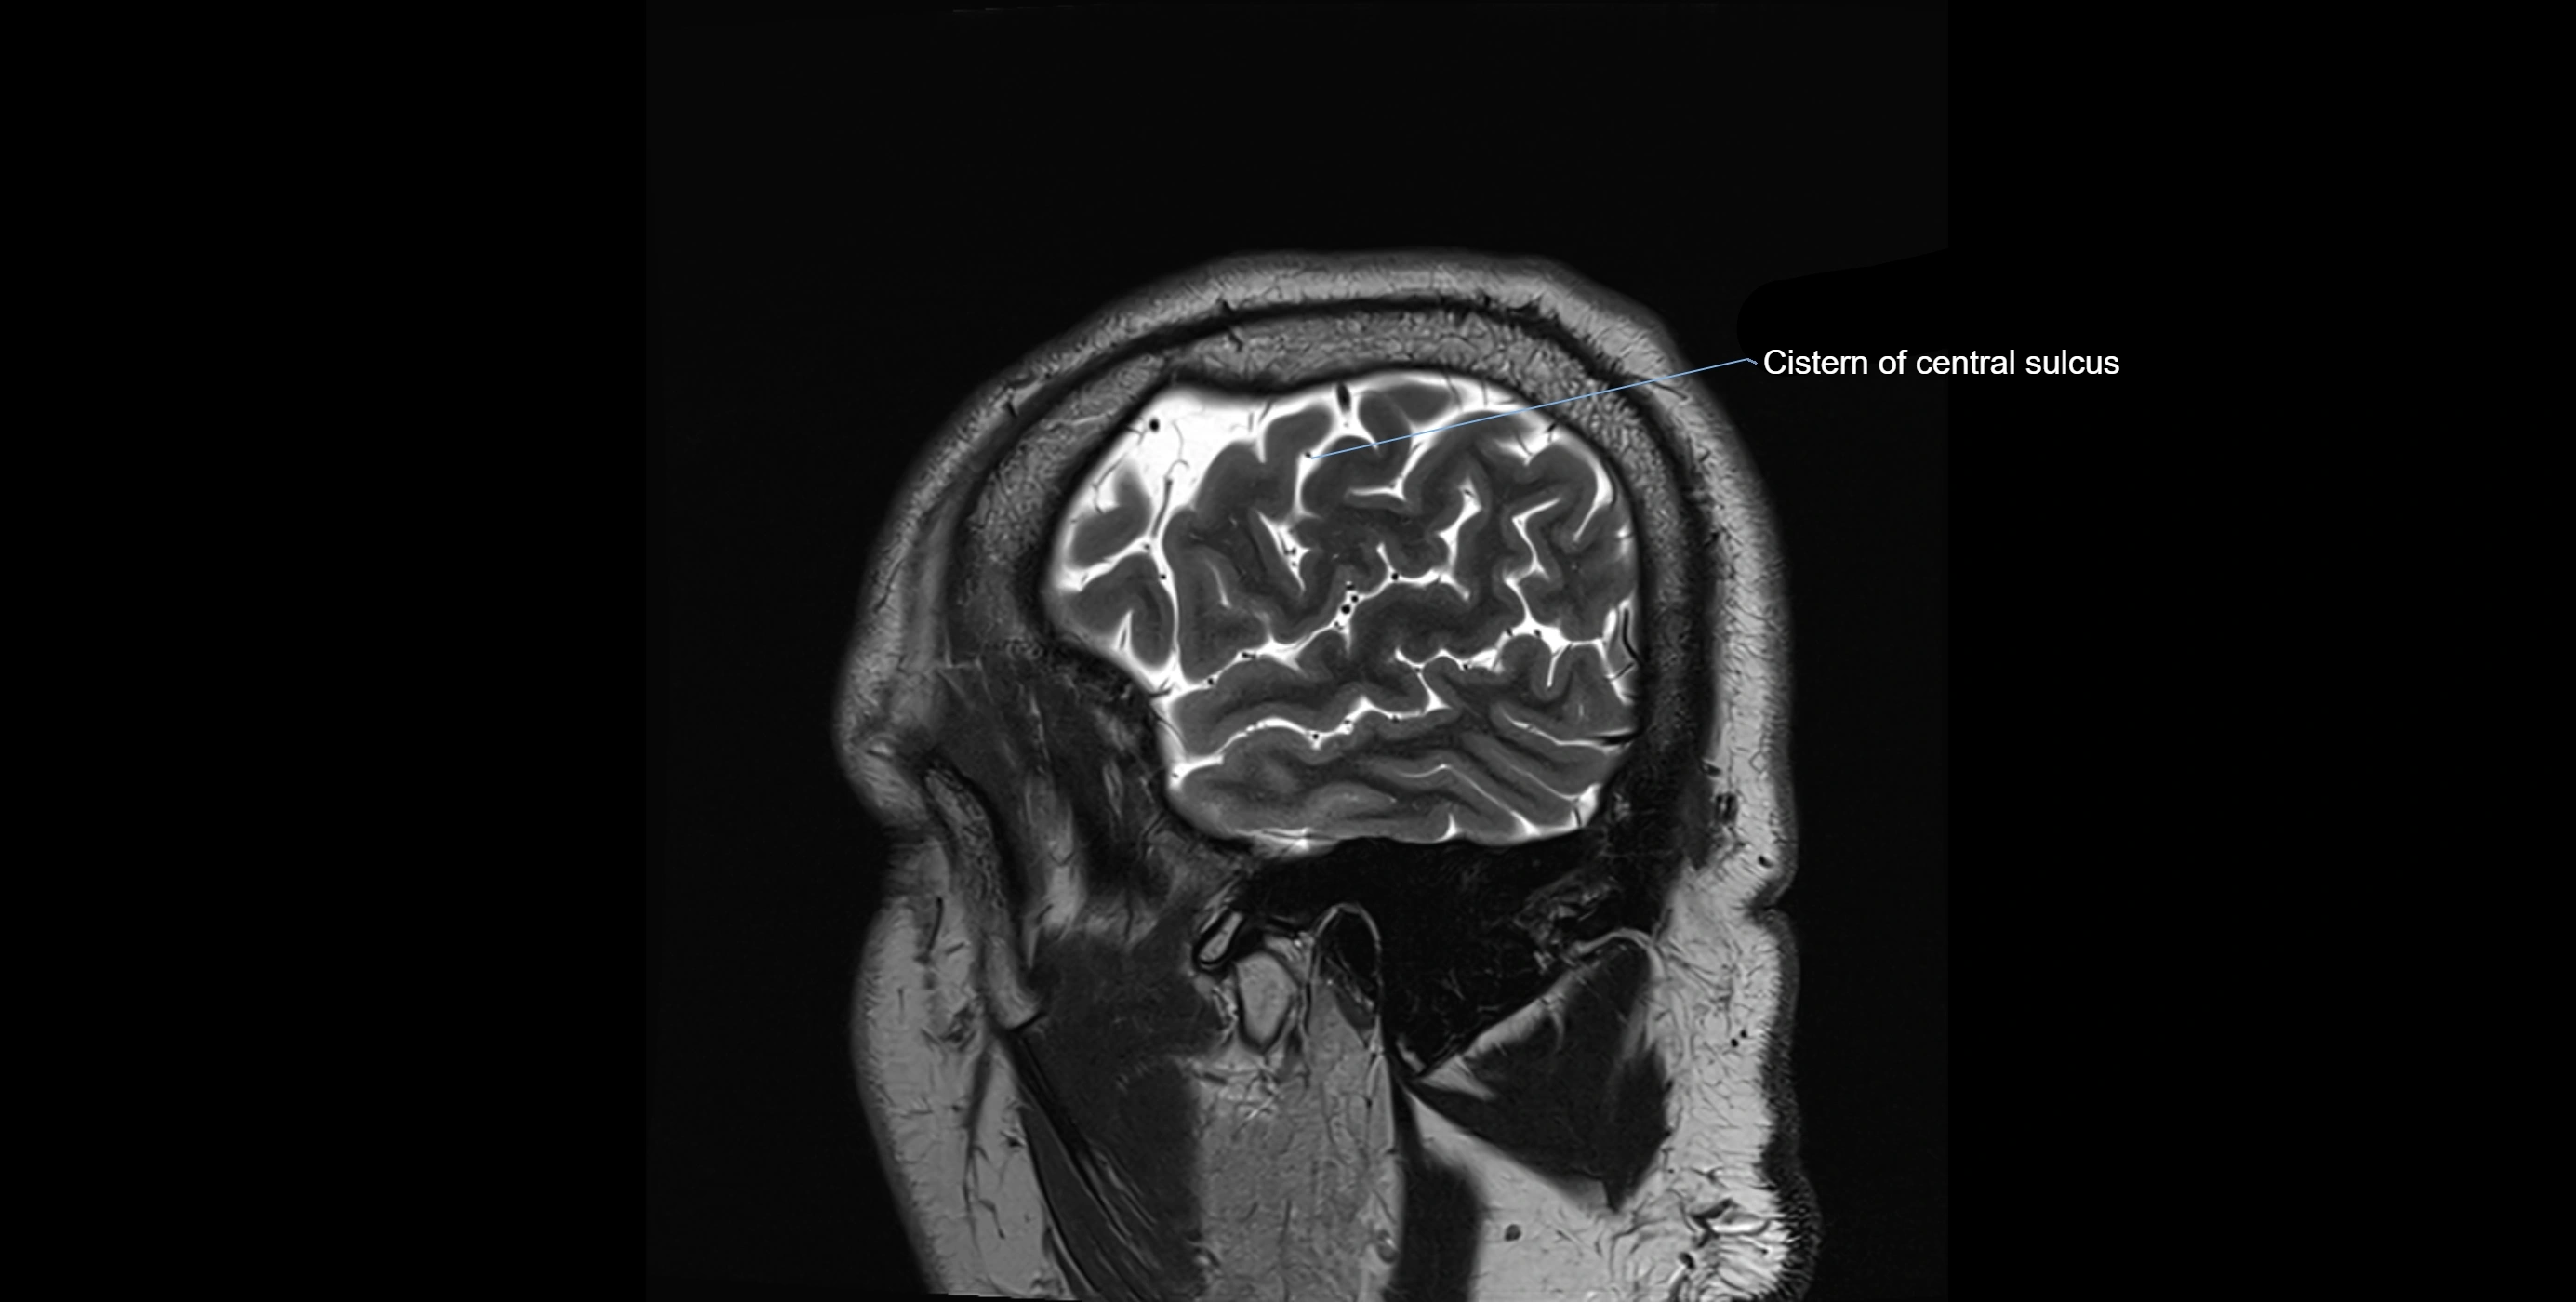

MRI images

image